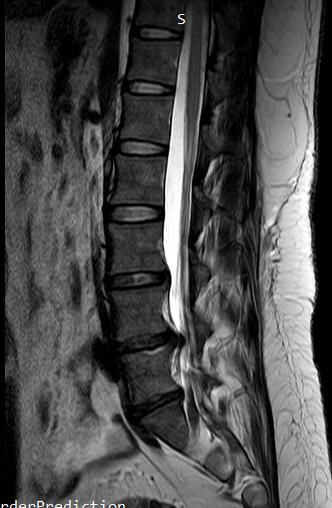

• 1번 째 사진

• 2번 째 사진